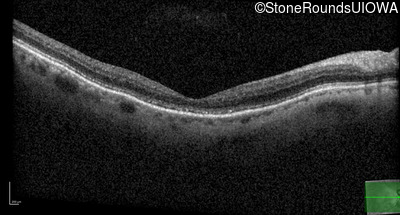

The clinical features favoring the diagnosis of RP1L1-associated occult macular dystrophy include: reduced acuity with a near-normal ophthalmoscopic appearance, a history of normal acuity in childhood; and, a "moth-eaten" appearance of the macular ellipsoid zone on OCT.

Age at visit: 75 years